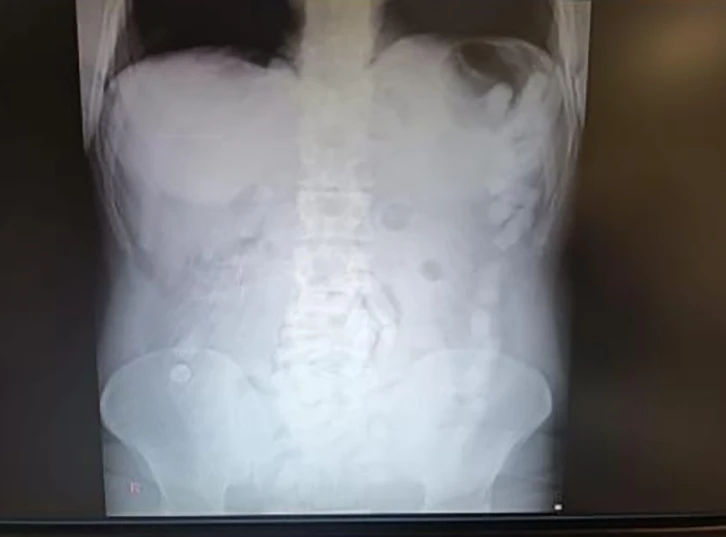

Kayseri'de polis ekipleri tarafından gözaltına alınan şahsın midesinden çıkarılan 100 kapsülde toplamda 729 gram uyuşturucu madde ele geçirildi.

Kayseri’de polis ekipleri tarafından gözaltına alınan şahsın midesinden çıkan 100 kapsülde toplam 729 gram uyuşturucu madde olduğu belirlendi.

Edinilen bilgiye göre, Kayseri İl Emniyet Müdürlüğü Narkotik Suçlarla Mücadele Şube Müdürlüğü ekipleri yabancı uyruklu bir şüphelinin ülkeye giriş yaparak Kayseri’ye geleceğini tespit etti. Şahsı takibe alan ekipler, yerini tespit ettikten sonra operasyon düzenledi. Kayseri Şehir Hastanesinde ultrason çekimi ile yapılan kontrolde şahsın midesinde çok suyada kapsül olduğu tebpit edildi. YApılan operasyonla şahsın midesinden çıkarılan 100 adet kapsülün içerisinde 729 gram uyuşturucu madde ele geçirildi. İşlemlerinin ardından adliyeye sevk edilen şüpheli, çıkarıldığı mahkemece tutuklanarak cezaevine gönderildi.